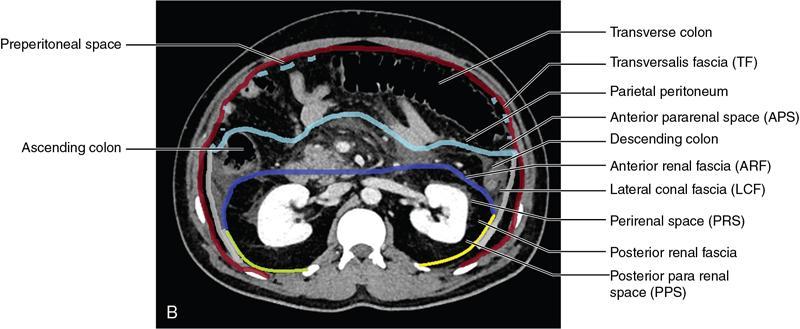

CROSS SECTIONAL ANATOMY OF ABDOMEN Satya Jha NORMAL ANATOMY OF ABDOMEN AND PELVIS Amandeep Singh The two major surfaces: The anterior and posterior layers of the coronary ligament converge on bare area (not covered by peritoneum). Its right and left margins form the right and left triangular ligaments. The right triangular ligament extends toward the diaphragm and separates right subphrenic space from right subhepatic space. The left triangular ligament gives tracts extending to the diaphragm and falciform ligament and does not compartmentalize the left subphrenic space. Ligamentum teres or the obliterated umblical vein is contained in falciform ligament which attaches the liver to anterior abdominal wall. The main portal vein, the proper hepatic artery and the common bile duct are contained within investing peritoneal folds of hepatoduodenal ligament at the porta hepatis (Fig. 7.2.2.1). Liver is divided into eight segments which are functionally independent and have their own vascular supply and biliary drainage. Arterial circulation: The branches of the hepatic artery accompanying the portal veins. Hepatic venous system: The right, middle, and left hepatic veins draining into IVC (Figs. 7.2.2.2 and 7.2.2.3). The gallbladder is a blind pear-shaped muscular membranous sac which is an embryologic derivative of the foregut, is a pouch lying along the undersurface of the liver. The gallbladder fossa is located in the plane of the interlobar fissure, which lies between the right and left hepatic lobes. Its major function is to store and concentrate bile which is produced by the liver. It measures approximately 4 cm in diameter when it is normally distended. Gallbladder is a smaller tubular structure in contracted state. The normal gallbladder wall thickness ranges from 1 to 3 mm. The gallbladder is divided into the fundus, body and neck. Infundibulum is present in the region of neck of the gallbladder, which is called the Hartmann pouch, where gallstones are usually impacted. Intrahepatic biliary radicles (IHBRs) scattered throughout the liver get confluent towards the hilum. They unite to form the right and left main hepatic ducts which further unite to form common hepatic duct (CHD) at the hilum. Common bile duct is formed by the union of cystic duct with common hepatic duct. The main pancreatic duct is joined with the common bile duct to form the ampulla of Vater at the major duodenal papilla (Figs. 7.2.2.4 and 7.2.2.5). Pancreas is located in anterior pararenal space of retroperitoneum anterior to perirenal (Gerota’s) fascia and posterior to parietal peritoneum. It is divided into head, uncinate process, neck, body and tail from right to left. Pancreas lies anterior to portal vein, which marks the point of transition between the body and neck. The region between head of pancreas and second and third parts of duodenum is known as the pancreatic groove. In postnephrectomy cases or with agenesis of kidney or ectopic kidney, pancreas moves posteriorly to partially fill in the empty renal fossa; its soft tissue density should not be mistaken for recurrent tumour. It is located in the pancreatic groove and is bounded superiorly by the duodenal bulb, laterally by second portion of duodenum, inferiorly by third portion of duodenum, medially by superior mesenteric vein and anterior to inferior vena cava. It is a wedge or wedge shaped lying posterior to superior mesenteric artery and vein. It is an imaginary junction between the head and body and lies directly over the junction of the splenic vein and superior mesenteric vein. It is located posterior to the lesser sac and anterior to the aorta, left adrenal gland, left kidney, and renal vessels and runs obliquely upward to the left of the superior mesenteric vessels. It is situated median to the colonic flexure and anterior to the left kidney. It is located in close proximity to the splenic hilum without a notable relation with the body of pancreas. It is seen anterior to the left kidney and median to the colonic flexure. The distal part of the tail passes between the peritoneal layers of the splenorenal ligament (Fig. 7.2.2.6 and 7.2.2.7).